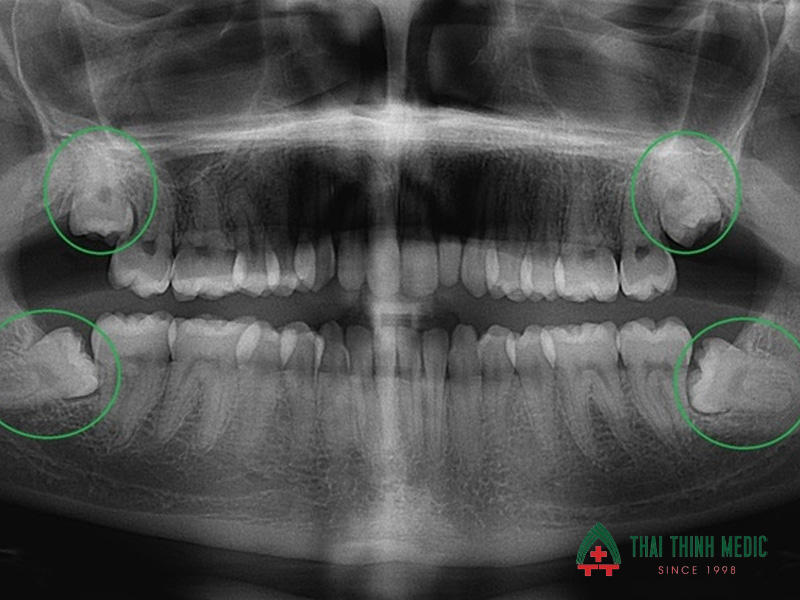

- Khám và chụp X-quang hoặc CT Conebeam để đánh giá vị trí răng, góc mọc, mức độ mọc ngầm và khoảng cách với dây thần kinh.

Chỉ xảy ra khi răng khôn nằm sát hoặc đè lên dây thần kinh hàm dưới. Nha sĩ sẽ chụp X-quang hoặc CT Conebeam để đánh giá trước khi nhổ, từ đó chọn kỹ thuật phù hợp nhằm tránh biến chứng tê môi – tê cằm. Tỷ lệ tổn thương thần kinh rất thấp nếu thực hiện tại cơ sở uy tín.